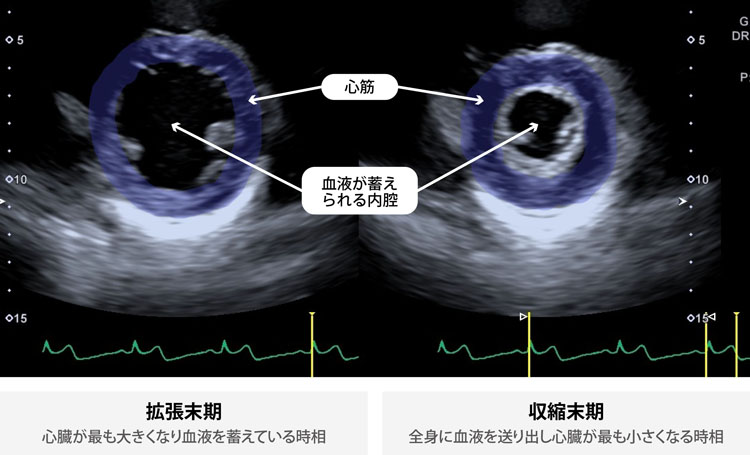

■正常な心臓

■心筋梗塞